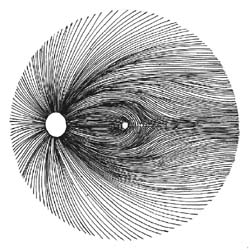

Kdybychom tak uměli spočítat množství gangliových buněk jako umíme změřit nitrooční tlak! To by se nám diagnostikoval glaukom! Na množství gangliových buněk můžeme jen usuzovat podle svazečků nervových vláken na sítnici a podle šíře neuroretinálního lemu terče zrakového nervu. Sledování změn vrstvy nervových vláken je citlivější pro včasné poznání glaukomu než sledování terče samotného. Vzhledem k variabilitě terče je obtížné stanovit jednotnou normu pro všechny lidi. Vrstva nervových vláken morfologicky je však téměř stejná u každého člověka!